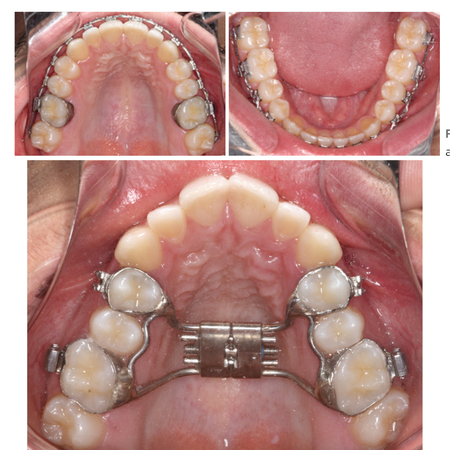

Impression for orthodontic band transfer for manufacturing soldered appliances on working models

INTRODUCTION: The impression for orthodontic band transfer is a critical step in the fabrication of orthodontic appliances soldered on working models. Inadequate band adaptation or errors during the impression procedure may compromise appliance seating, increase the risk of deformation, and favor band fracture during activation. OBJECTIVE: The aim of this study was to present a simplified and predictable clinical protocol for band transfer impression, based on the use of soldered...